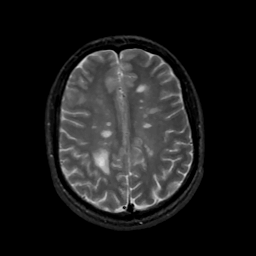

MR Study #7, March 24, 1991 -- Slice #34